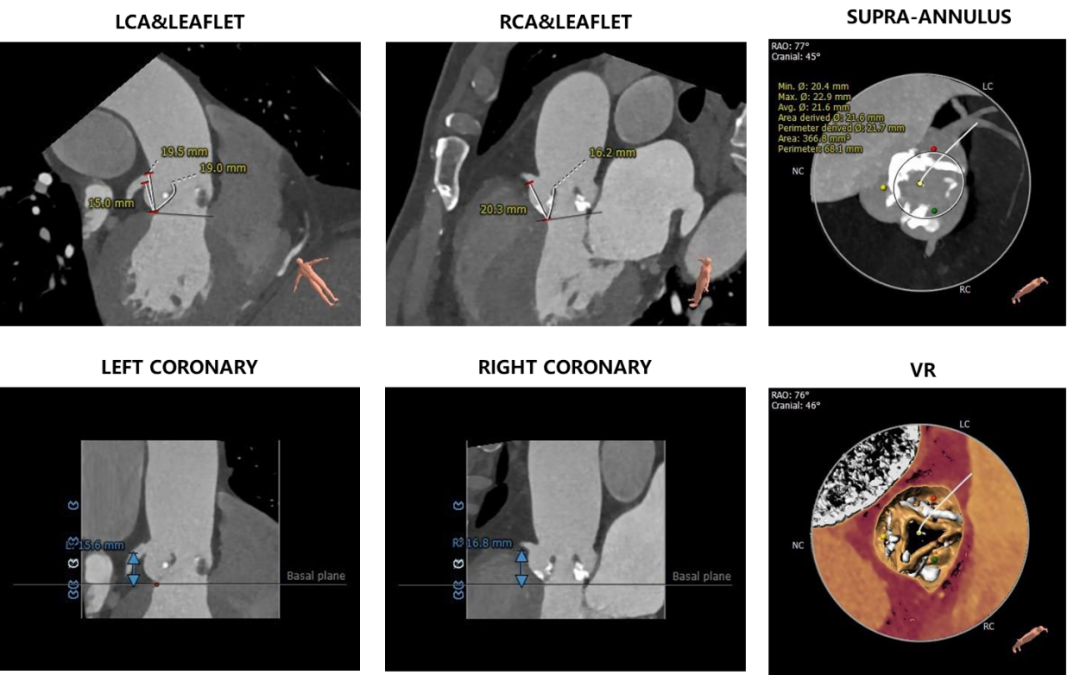

术前CT评估

三叶式主动脉瓣,重度钙化,钙化主要分布在瓣叶边缘及附着缘,分布不均,左无窦钙化重,右窦钙化相对较轻,瓣叶明显增厚,左无窦交界钙化性粘连,

冠脉开口高度可,左冠瓣瓣叶长度>冠脉开口到瓣叶附着缘距离;冠脉散在钙化,

瓦氏窦内径尚可,窦管交界、升主动脉内径可,

瓣环平面与水平面夹角44°,非横位心,主动脉弓宽度及角度尚可。流出道呈敞口型,左室心腔内径尚可,

主动脉根部测量

冠脉高度、瓣叶长度及钙化测量

瓣环上测量